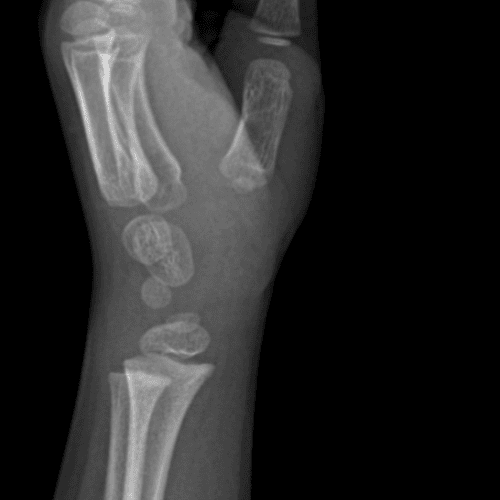

Simulates call by including subtle or difficult cases and some normals.

40 cases